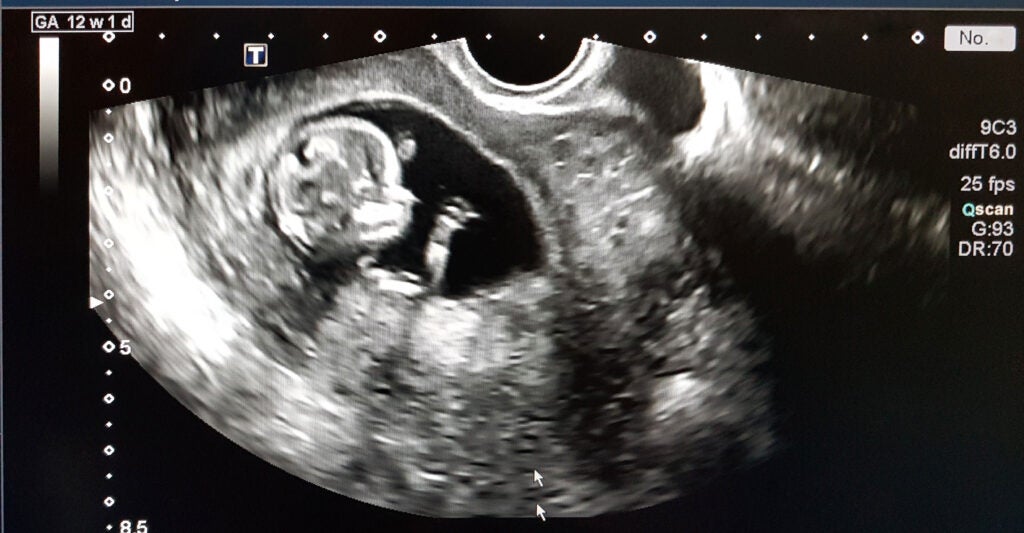

The chemical abortion pill regimen is a two-part process. The first pill, mifepristone (also known as RU-486 or its brand name, Mifeprex), causes the death of the unborn child by cutting off the hormone progesterone, which is required to sustain a pregnancy.

The second pill, misoprostol (brand name Cytotec), causes contractions to empty the uterus. The regimen is approved to be used for up to 70 days (10 weeks) into pregnancy.

Neither can a prescriber precisely date a pregnancy, meaning more women might be prescribed an abortion pill well past 70 days gestation (a serious risk itself, as the risks from a chemical abortion increase the farther along in pregnancy she is).

This article’s photo caption has been updated to correct the description of mifepristone